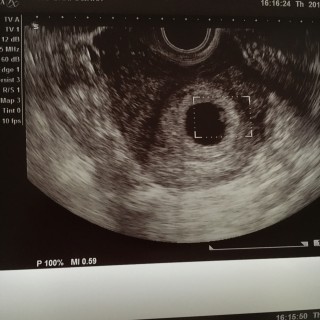

本当は1週間後の検診予定でしたが、妊娠悪阻が酷く、ケトン体が出てしまったのでこの日点滴をして、最後に念の為見てみましょうとの事でエコーをしてもらったら、予想外にもう心拍確認が出来ました。すんごく小さいけどピコピコしてる心臓や、心拍の音を聞いて感動で感極まってしまいました(*^^*) 赤ちゃんは胎嚢19.7mm、胎芽2.5mmでした。どうかこのまますくすく育ってくれますように☆